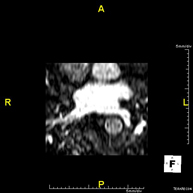

Prova diagnòstica no invasiva que consisteix en l'obtenció d'imatges d'alta definició anatòmica de les artèries cerebrals mitjançant l'ús d'un camp electromagnètic i ones de ràdio (com un emissor i un receptor). No utilitza radiació ionitzant. En la majoria dels casos és necessari l'us de contrast paramagnètic (Gadolino). Permet un estudi angiogràfic no invasiu gràcies a la injecció de Gadolino amb una reconstrucció posterior en 2D i 3D gràcies a estacions de treball especialitzades. Indicacions: malformacions vasculars, aneurismes d'artèries cerebrals, arteriosclerosi. - Angio-RM de troncs supraaòrtics

Prova diagnòstica no invasiva que consisteix en l'obtenció d'imatges d'alta definició anatòmica de les artèries cerebrals mitjançant l'ús d'un camp electromagnètic i ones de ràdio (amb un emissor i un receptor). No utilitza radiació ionitzant. En la majoria dels casos és necessari l'ús de contrast paramagnètic (Gadolini). Permet un estudi angiogràfic no invasiu gràcies a la injecció de Gadolini amb posterior reconstrucció en 2D i 3D, gràcies a estacions de treball especialitzades. Indicacions: malformacions vasculars, aneurismes d'artèries cerebrals i arteriosclerosi. - Angio-RM de Troncs supraaòrtics